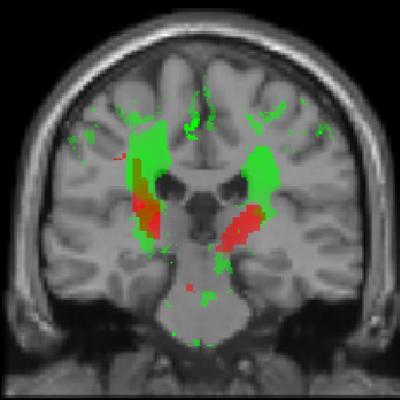

The scientists studied 13 patients with acute spinal cord injuries every three months for a year using novel MRI (magnetic resonance imaging) protocols. They discovered that the diameter of the spinal cord had rapidly decreased and was already seven percent smaller after twelve months. A lesser volume decline was also evident in the corticospinal tract, a tract indispensable for motor control, and nerve cells in the sensorimotor cortex. The extent of the degenerative changes coincided with the clinical outcome. "Patients with a greater tissue loss above the injury site recovered less effectively than those with less changes," explains Patrick Freund, the investigator responsible for the study at the Paraplegic Center Balgrist.

This shows MRI protocol. Red: This shows dynamic tissue loss in the corticospinal tract and sensorimotor cortex after twelve months of spinal cord injury. Green: These are spots with reduced myelin layer.